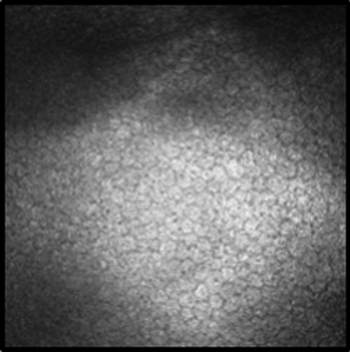

Figures 1a & 1b. Slit-scanning in vivo confocal microscopy images of the corneal endothelium: A) Healthy control cornea: Image of a normal corneal endothelium, showing a uniform hexagonal cell pattern with consistent cell density and no visible guttae or abnormalities (white solid arrowhead). B) FECD: Increased confluency of guttata, illustrating a more extensive presence of these structures.